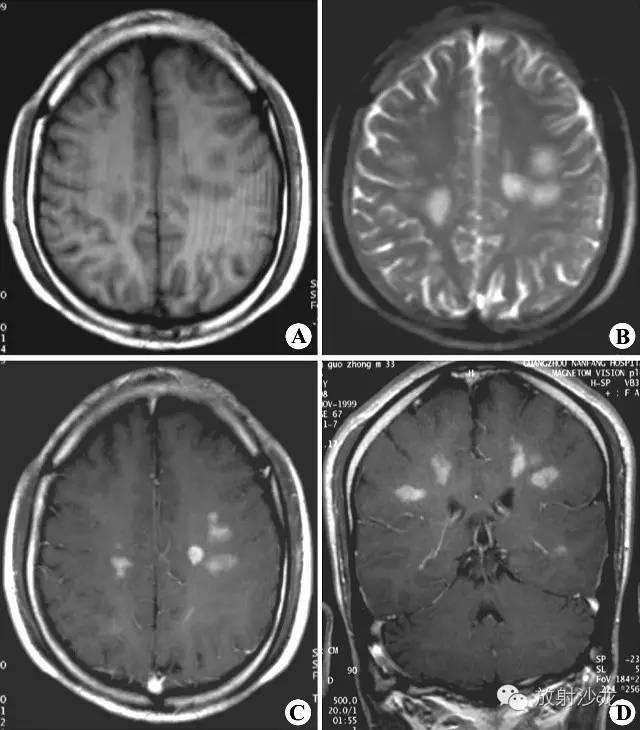

1.2影像学:MRIT1加权像见多发斑点状低信号病灶,通常与侧脑室壁垂直排列,与脑室周围白质内小血管的走行方向一致。陈旧性斑块呈等信号。由于多发硬化是少突神经胶质-血管髓磷脂复合疾病,因此有5%者,皮质和基底节亦受累,半卵圆中心的病灶可有占位效应。脊髓病灶呈长 条形,与脊髓长轴走行一致,一般脊髓不增粗。T2加权像病灶呈高信号,边缘清晰。质子密度加权像有利于显示靠近脑室边缘、脑干及小脑MS病灶。Gd- DTPA增强扫描T1加权像急性脱髓鞘病灶强化,陈旧病灶无强化。 MRI可判断MS的分期:MRI显示病灶大小不变、病灶缩小或数目减少,则提示为缓解期;若病灶增大或数目增多,则提示病情加重。MRI还可用来随访治疗效果。

MRI平扫示双侧半卵圆区多发斑片状异常信号区,呈长T1(A)和长T2(B)改变;增强扫描(C、D)病变明显强化

双侧幕上半球放射冠区多发斑片状异常信号区。T1WI(A)为稍低信号,T2WI(B)为高信号,FLAIR(C)呈不均匀稍高信号,占位效应不明显。

肿块样的ms,但较之肿瘤水肿轻,和对白质压迫的作用。